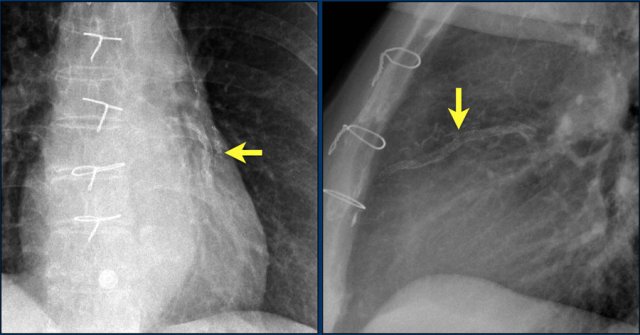

First study the images.

Then continue reading.

The findings are:

• Two epicardial leads connected to pacemaker

• ICD

• two leads to right ventricular apex

• one lead contains two shock coils

• tricuspid valve (arrows)

• mitral valve